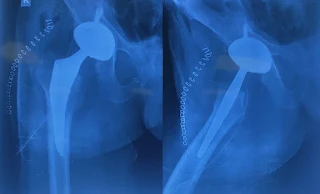

We performed a metal-on-poly Total Hip Replacement (THR) via the posterior approach to reduce the patient cost. The plan was to retain the posterior plate, but as is often the case, bones have their own plans. The plate obstructed the optimal placement of the acetabular cup, so we had to remove it.

Implants used:

- 54 mm acetabular cup

- 54 mm elevated polyethylene liner

- 36 mm (+offset) femoral head

- Size 7 femoral stem